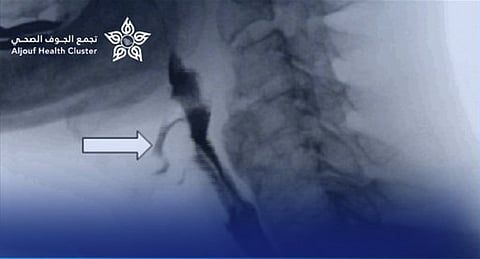

وأوضح التجمع الصحي بمنطقة الجوف أن الطفل كان يعاني من صعوبة شديدة في البلع واسترجاع متكرر للطعام، وتبيّن بعد الفحوصات وجود تضيق شديد في المريء يعيق مرور الطعام. وقد قام الفريق الطبي بإجراء عملية توسيع للتضيق باستخدام المنظار والموسعات الطبية المناسبة، تكللت بالنجاح الكامل دون أي مضاعفات.